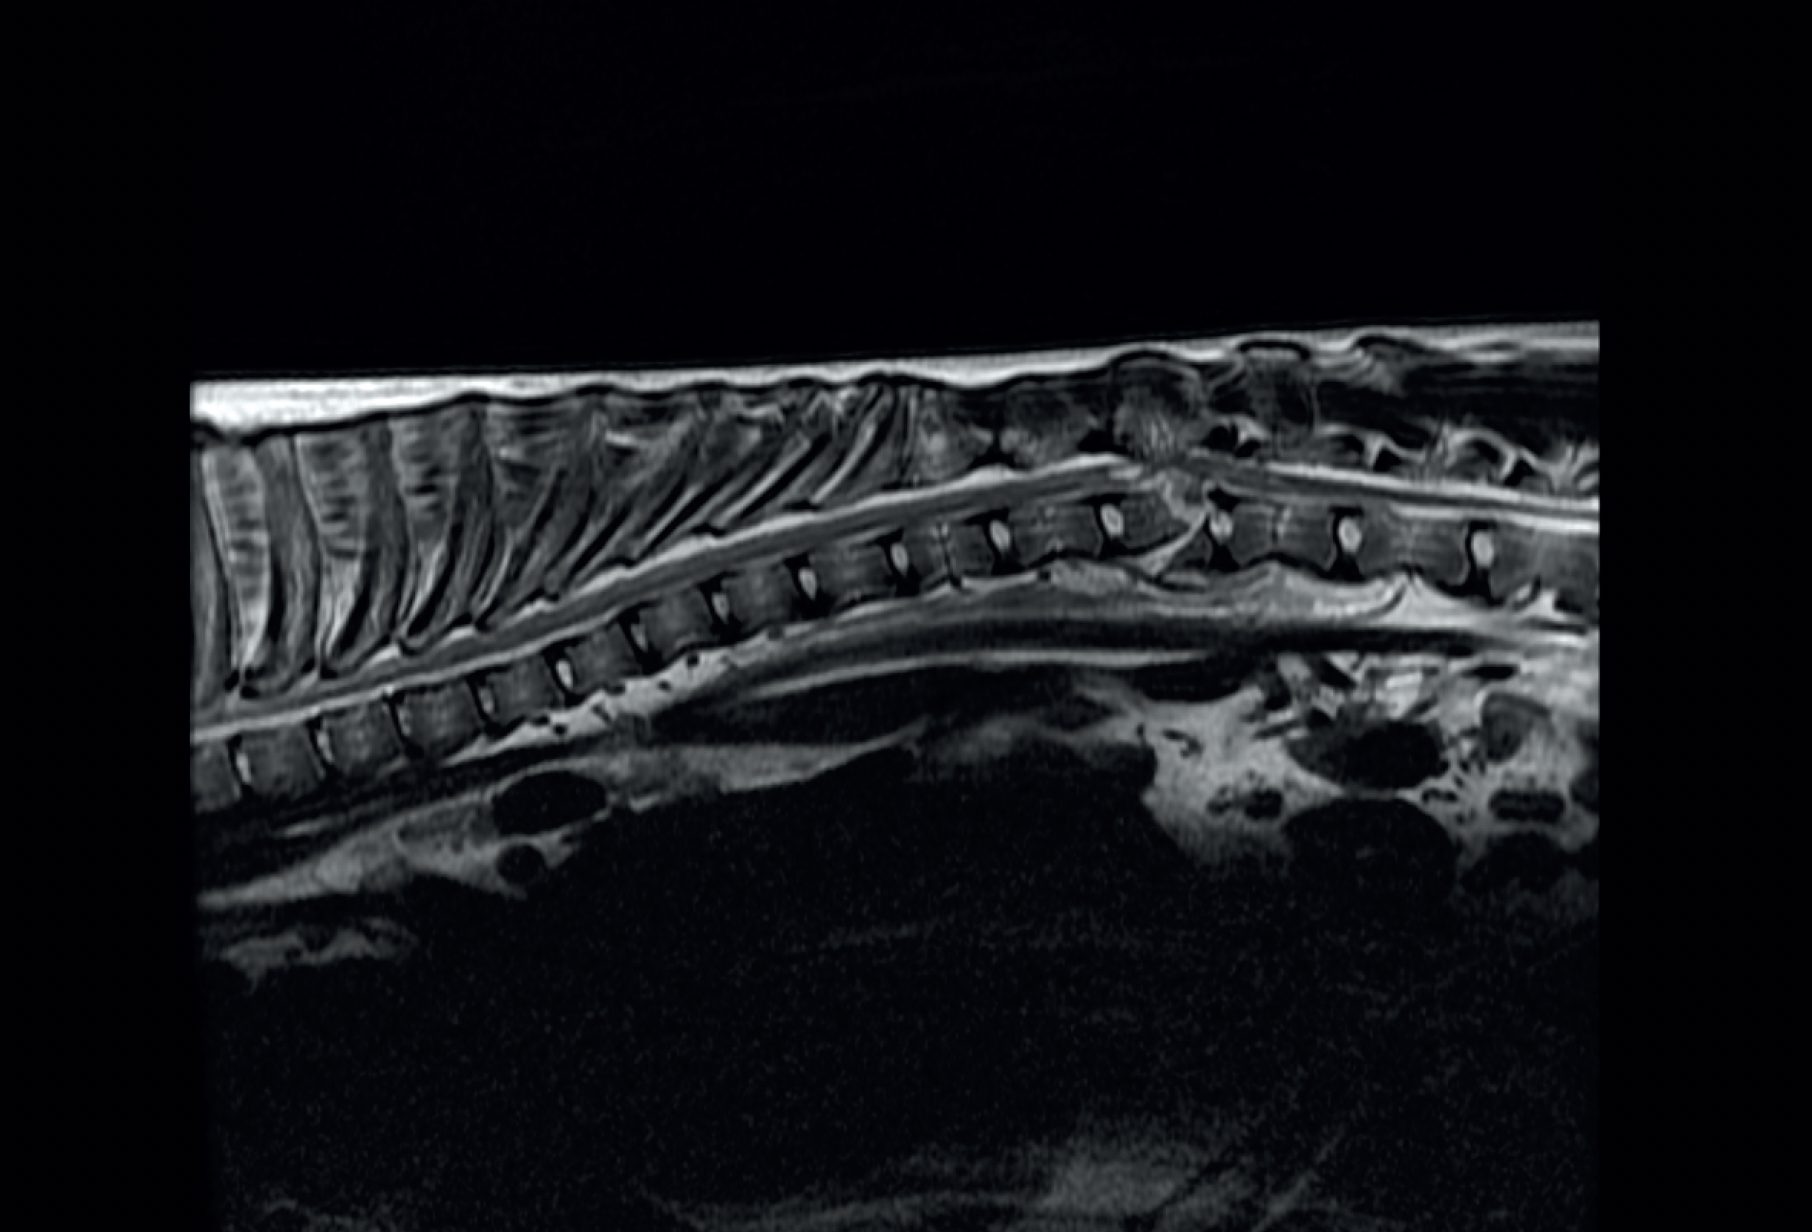

Diagnostyka obrazowa mózgu i kręgosłupa

Zrozumiesz lepiej kryteria wyboru pomiędzy RTG, CT i MRI — w zależności od przypadku.

Zdobędziesz cenne doświadczenie w analizie obrazów na rzeczywistych przypadkach klinicznych